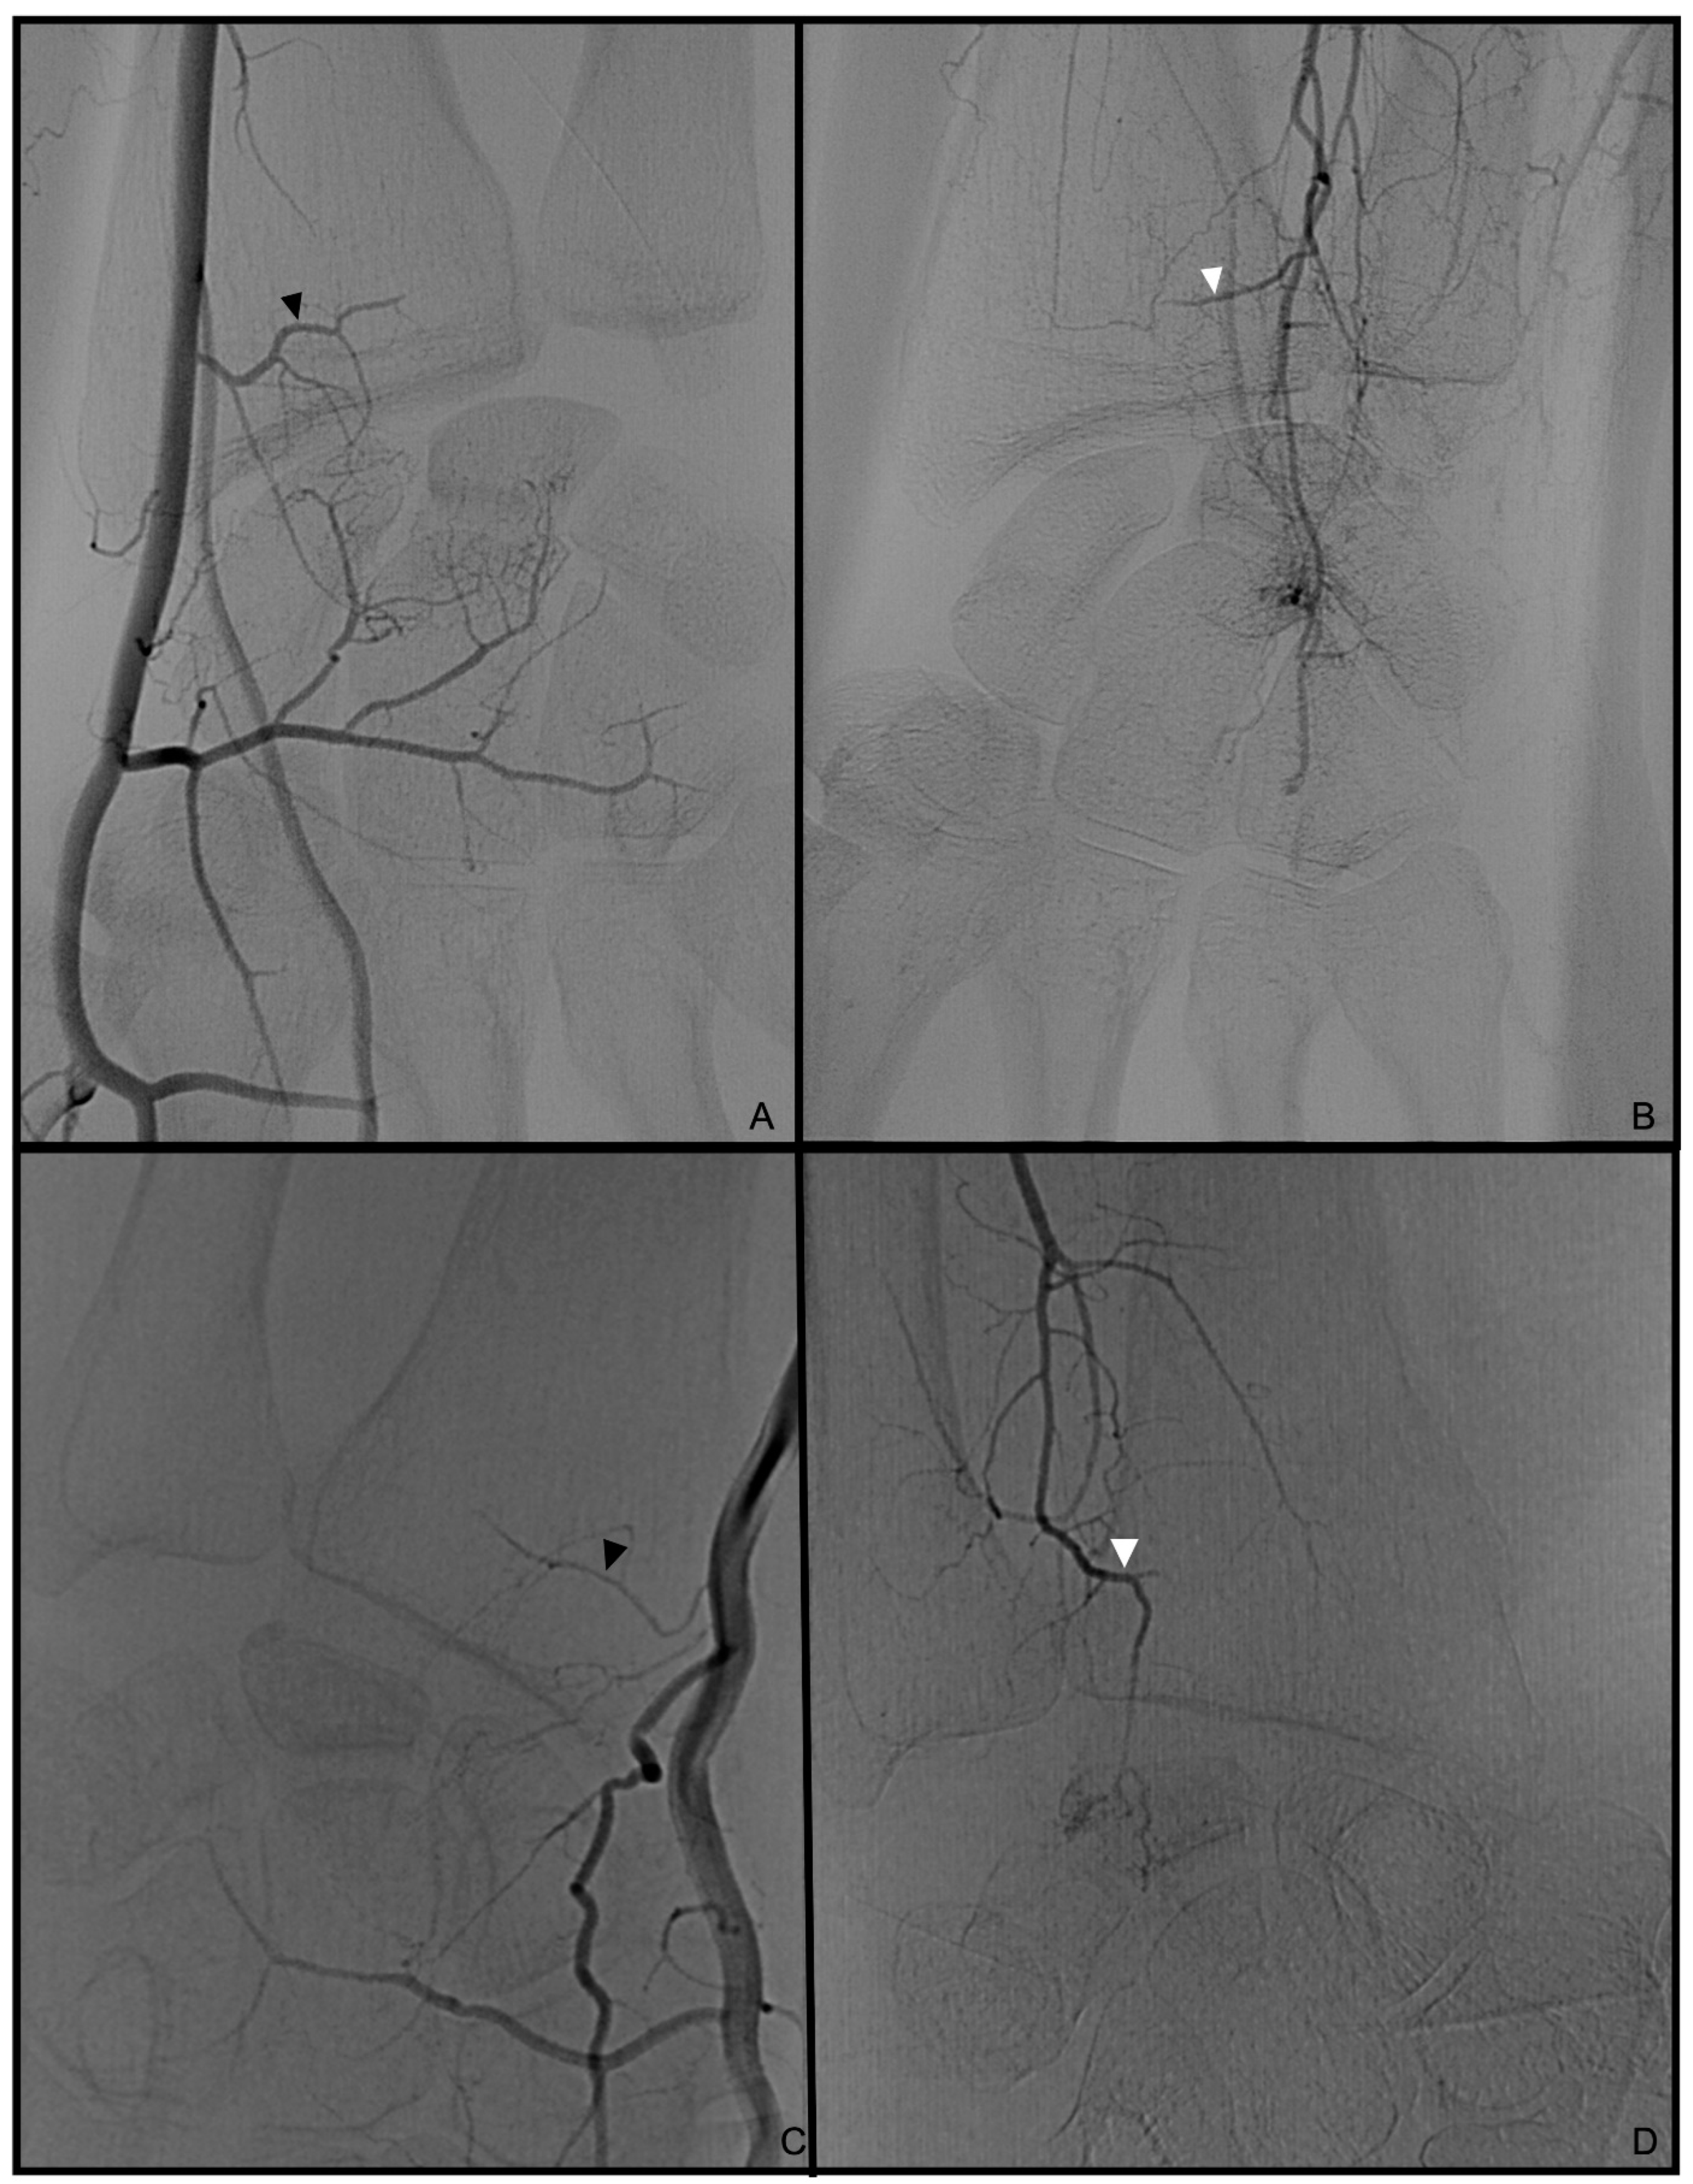

3.1. Palmar Radiocarpal Artery and Palmar Radiocarpal Arch (PRCA)

3.2. Dorsal Carpal Branch of the Ulnar Artery (DCBUA)

3.3. Anterior Interosseous Artery (AIA)

3.4. Treatment Strategies